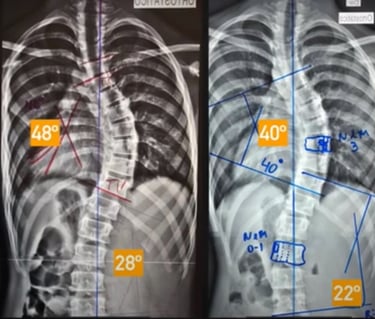

Após receberem o diagnóstico de escoliose, essa família buscou a opinião de diversos ortopedistas renomados, todos unânimes em recomendar a cirurgia de artrodese como única solução.

Aqui, após uma avaliação especializada e detalhada, foi possível substituir o antigo colete Milwaukee — que já não apresentava evolução — por um moderno colete 3D, desenvolvido com base na tecnologia de escaneamento corporal e evidências científicas.

Paciente Adolescente

O resultado?

➡️ Redução de 8° na curvatura torácica

➡️ Redução de 6° na curvatura lombar

Sem cirurgia. Sem internações. Apenas com a combinação de tecnologia avançada, atendimento especializado e a determinação da família.